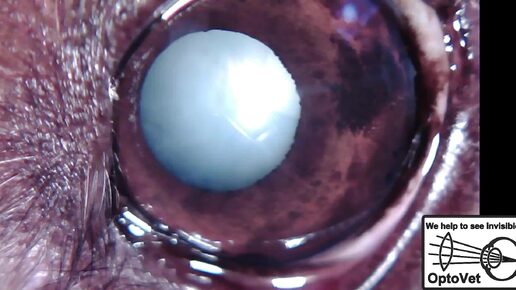

Возрастная катаракта у собак